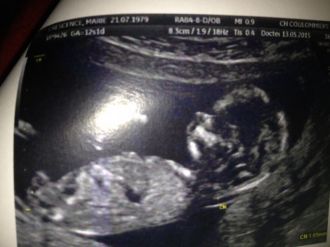

Et notre surprise !C'était lors de la première échographie du 12 mai 2015. Nous avions du mal à y croire....Tout va bien...  Message déposé le 12.06.2015 à 19:25 - Commentaires (2)